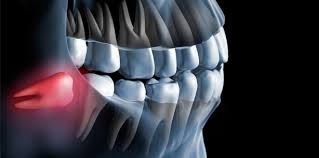

Von der Wuchsrichtung des Zahnes davon wie viel von dem jeweiligen Zahn bereits im Kiefer angelegt und verwachsen war und. Verläuft der Durchbruch der Weisheitszähne bei einigen Menschen ohne Komplikationen so leiden andere unter starken Schmerzen und Entzündungen die sich über mehrere Monate hinweg ziehen. Schmerzen nach dem Ziehen der Weisheitszähne.

Wie stark die Schmerzen sind und wie lange sie andauern hängt von einigen Faktoren ab. Dann allerdings sollten diese langsam abklingen. Bei den meisten Entfernungen der Weisheitszähne entstehen nur leichte Schmerzen oft hat man überhaupt keine.

Es dauert je nach der Größe des Weisheitszahns und sonstigen Faktoren recht lange bis die Wunde vollständig verheilt ist. Das durchschnittliche Alter in dem die Weisheitszähne durchbrechen beträgt etwa 16 Jahre. Es kann 7-14 Tage dauern bis sie vollständig abklingen.

Dann allerdings sollten diese langsam abklingen. Ist das nicht der Fall und verstärken sich die Schmerzen sogar sollte dringend der Zahnarzt aufgesucht werden. Ablauf Ablauf was Sie beachten müssen. Schmerzen nach Weisheitszahn OP wie lange normal. Wie lange dauern die Schmerzen normalerweise an. Es kann 7-14 Tage dauern bis sie vollständig abklingen. Die Fäden zieht der Zahnarzt in der Regel nach 7-10 Tagen. Mit welchem Alter brechen die Weisheitszähne durch. Die Schmerzen nach einer Weisheitszahn OP können 7 bis 14 Tage anhalten allerdings mit abklingender Intensität.

Dies hängt natürlich hauptsächlich von der Schwere des Eingriffs ab. Die Schmerzen können jedoch schon unmittelbar nach einigen Stunden nach dem Eingriff abklingen. Auch am nächsten Tag muss meist noch mit Schmerzen gerechnet werden. Wie lange dauern die Schmerzen nach einer Weisheitszahn-OP. Nach der Entfernung der Weisheitszähne sind die Wangen und der Mundbereich bei den meisten Patienten geschwollen. Verläuft der Durchbruch der Weisheitszähne bei einigen Menschen ohne Komplikationen so leiden andere unter starken Schmerzen und Entzündungen die sich über mehrere Monate hinweg ziehen. Dies hängt natürlich hauptsächlich von der Schwere des Eingriffs ab.